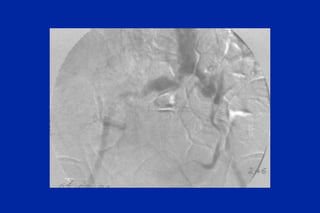

Este documento resume los principales tipos y técnicas de angiografía. Describe brevemente la angiografía, arteriografía, flebografía y linfografía, así como las técnicas de contraste y materiales utilizados. También explica los principales accesos vasculares, la técnica de Seldinger, la angiografía por sustracción digital y algunas técnicas endovasculares comunes.